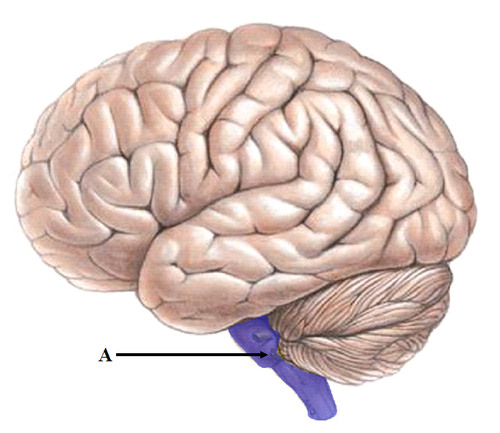

brainstem

The oldest part and central core of the brain, beginning where the spinal cord swells as it enters the skull; the brainstem is responsible for automatic survival functions.

cerebellum

The "little brain" at the rear of the brainstem; functions include processing sensory input, coordinating movement output and balance, and enabling nonverbal learning and memory.